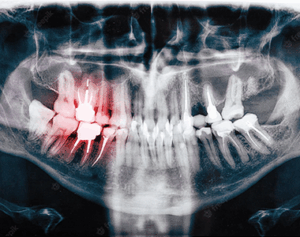

Maintaining good oral health is crucial for overall well-being. However, despite regular brushing and flossing,…